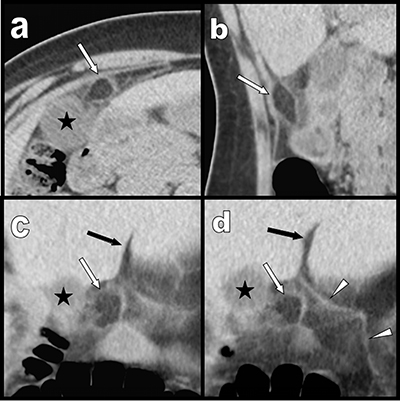

Figure 1

Case 1: transverse (a), sagital (b) and coronal oblique (c) and (d) multiplanar reconstructions show a pre-hepatic area of fat stranding surrounding a 1,5 cm well demarcated inflammatory lipomatous process (white arrows) just under the hepatic fissure (black arrow) and in very close vicinity of the right edge of the ligamentum teres (white arrowheads). Black star = gallbladder.